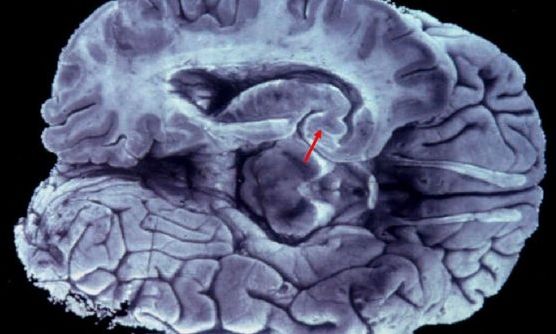

Εγκάρσια τομή ανθρώπινου εγκεφάλου, με ένδειξη σε περιοχή όπου οι ερευνητές εντόπισαν πιθανές άγνωστες αγγειακές δομές που ενδέχεται να σχετίζονται με την απομάκρυνση μεταβολικών αποβλήτων

Μια τυχαία αλλά ενδεχομένως καθοριστική ανακάλυψη στον ανθρώπινο εγκέφαλο φέρνει νέα δεδομένα στη μελέτη της νόσου Αλτσχάιμερ και άλλων νευροεκφυλιστικών παθήσεων. Ερευνητές του Χάρβαρντ εντόπισαν άγνωστες έως σήμερα αγγειακές δομές, οι οποίες ενδέχεται να συμμετέχουν στην απομάκρυνση μεταβολικών αποβλήτων από το κεντρικό νευρικό σύστημα.

Η μελέτη, που δημοσιεύθηκε στην πλατφόρμα bioRxiv, ξεκίνησε με στόχο την ανάλυση συσσωρεύσεων β-αμυλοειδούς σε ζωικά μοντέλα με παθολογία παρόμοια με τη νόσο Αλτσχάιμερ. Κατά τη διάρκεια των πειραμάτων, ο ερευνητής Shiju Gu παρατήρησε τυχαία σωληνοειδείς σχηματισμούς, οι οποίοι δεν αντιστοιχούσαν σε καμία γνωστή ανατομική δομή. Οι σχηματισμοί αυτοί εντοπίστηκαν σε περιοχές όπως ο φλοιός, ο ιππόκαμπος και ο υποθάλαμος - περιοχές που σχετίζονται με τη μνήμη, τη λογική και τη ρύθμιση βασικών λειτουργιών.

Οι επιστήμονες εκτιμούν ότι οι δομές αυτές περιβάλλουν αιμοφόρα αγγεία και πιθανώς συνδέονται με τα λεμφικά αγγεία των μηνίγγων, γεγονός που υποδηλώνει ότι θα μπορούσαν να αποτελούν μέρος ενός άγνωστου έως τώρα εσωτερικού δικτύου αποστράγγισης. Προτείνουν μάλιστα τον όρο «λεμφικά αγγεία νανοκλίμακας» (NLV), αποκλείοντας -τουλάχιστον προς το παρόν- το ενδεχόμενο να πρόκειται απλώς για αποθέσεις πρωτεϊνών.